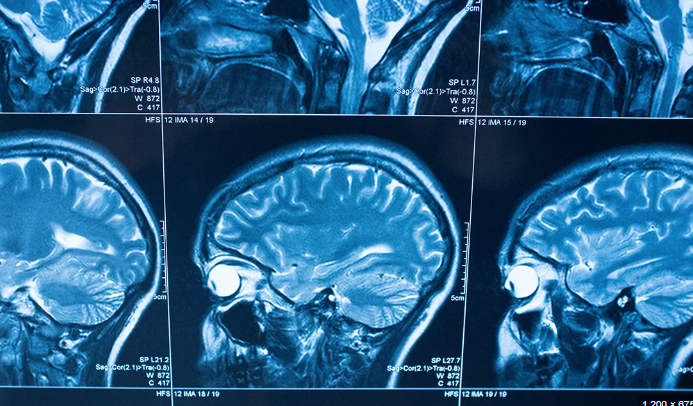

• MRI for CNS, spleen, lymph nodes, aorta (vasculitis)